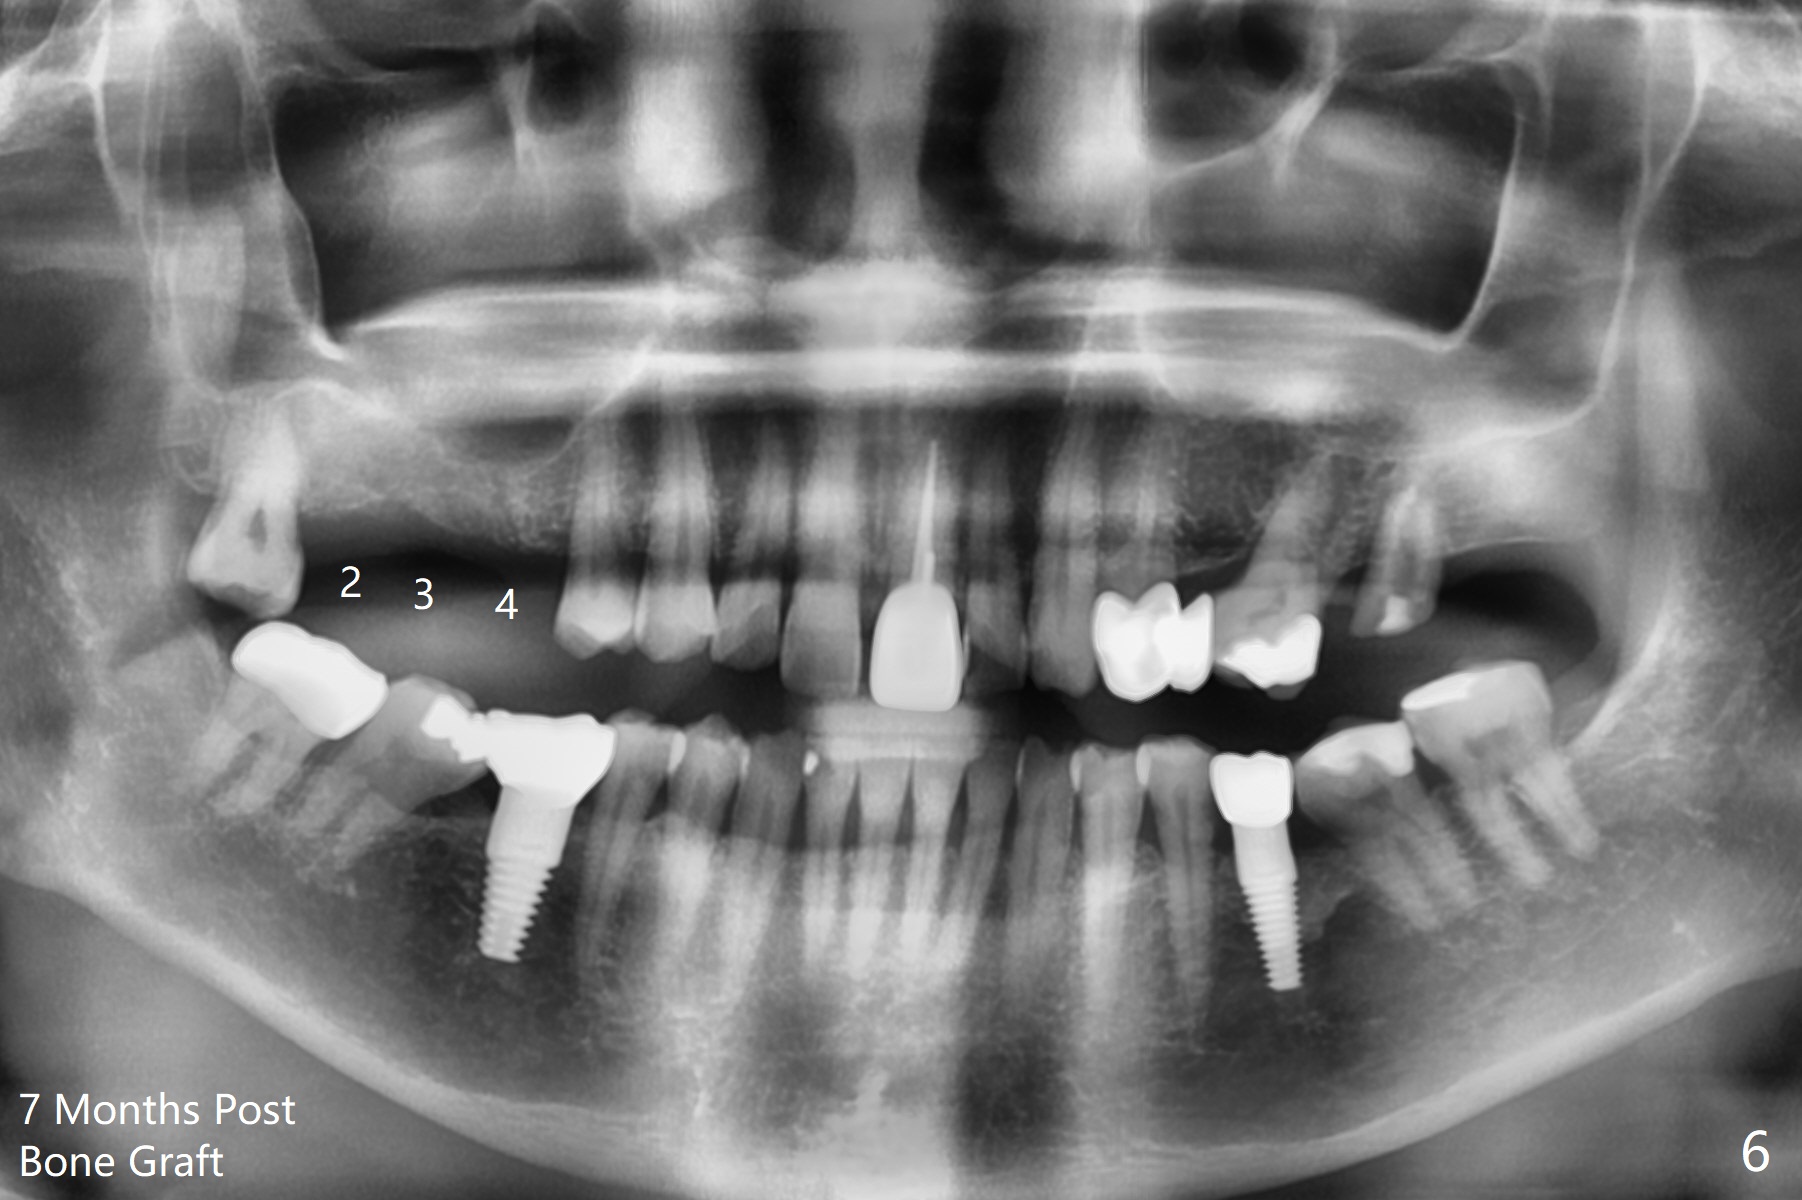

A 57-year-old woman returns with pain in the upper right quadrant (Fig.1,2). In fact the mesiobuccal root of the tooth #2 has vertical fracture. Although the socket destruction at #3 is not as extensive as that of #2, the socket of #3 has communication with the sinus. Prior to socket preservation, a piece of Osteogen plug is inserted at #3. PRF should be prepared for severe bone loss. In contrast there is no bone loss around the implants at #19 or #30 (Fig.1,3,4). Although the socket at #2 is slightly open 9 days postop, bone graft appears to be present (Fig.5). The bone at #2 and 3 seems to regenerate 7 months post socket preservation (Fig.6). Three short implants seem to be better than 2 implants for 3-unit FPD (Fig.7-9).